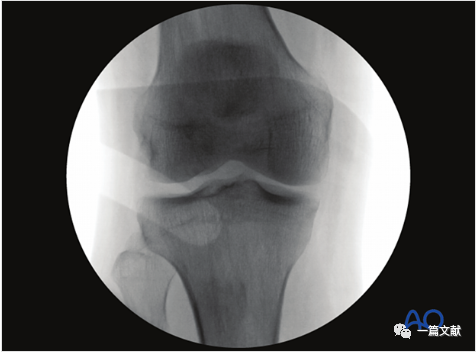

2)标准侧位的评估:1、股骨髁在图像的前方、后方、远端均重叠2、股骨髁位于图像中央 3,C臂机射线平行于胫骨关节面照射。如下图:

3)解剖标志的识别:如下图:1、外侧平台关节面(凸面)2、内侧平台关节面(凹面)3、髁间脊4、胫骨结节5、闭合的骨骺线

4)标准侧位的意义:1、评估内侧和外侧平台复位情况;2、评估胫骨髁间脊复位情况;3、评估胫骨平台是否存在相对于股骨向前或向后的半脱位(表明交叉韧带损伤);4、检视是否存在突入关节的内植物。